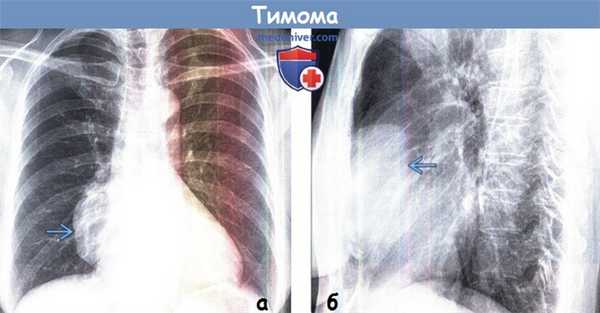

(а) У пациента с тимомой при рентгенографии органов грудной клетки в ПП проекции в правой половине средостения определяется объемное образование с четким дольчатым контуром. При рентгенографии в прямой проекции тимомы обычно проявляются изменением контура средостения.

(б) У этого же пациента при рентгенографии органов грудной клетки в боковой проекции видно, что тимома располагается в переднем средостении. Рентгенография в боковой проекции позволяет установить локализацию объемного образования в одном из трех отделов средостения и сузить дифференциальный ряд заболеваний.